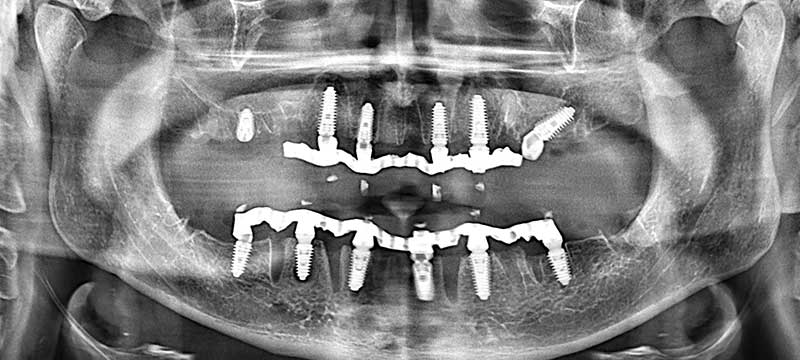

Имплантация проводилась с использованием корейской системы имплантов Megagen AnyRidge по протоколу All-on-6. Это когда зубной протез крепится на 6-ти имплантах. При данной методике нагрузка равномерно распределяется между имплантами, позволяет пациенту жить полноценной жизнью сразу же после протезирования (3-8 дней).

Хирургический этап занял чуть более 2.5 часов. Были удалены остатки зубов и вживлены импланты. Ортопедический этап потребовал 3 визита и 6 часов.

На хирургическом этапе вживлены 12 имплантов Megagen AnyRidge по протоколу All-on-6